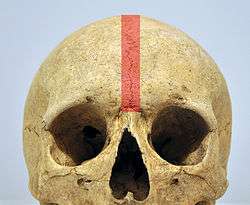

In some individuals the suture can persist (totally or partly) into adulthood, and in these cases it is referred to as a persistent metopic suture. The suture can either bisect the frontal bone and run from nasion to bregma or persist as a partial metopic suture (see image of frontal bone)[4] (where part of the suture survives and is connected to either bregma or nasion) or as an isolated metopic fissure. Persistent frontal sutures are of no clinical significance, although they can be mistaken for cranial fractures.[5] As persistent frontal sutures are visible in radiographs, they can be useful for the forensic identification of human skeletal remains. Persistent frontal sutures should not be confused with supranasal sutures (a small zig-zag shaped suture located at and/or immediately superior to the glabella).

| Outer surface of frontal bone, adult human skull. ("Remains of frontal suture" identified at center.) |